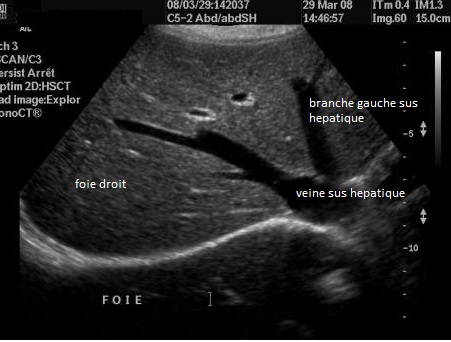

Coupe transverse

recurrent VHS a travers le foie et les trois

branches du veine sus hepatique |

Coupe

intercostale de la ligne axilaire anterieuse droit ( long sagitale

- vesiculaire ) . Foie droit , branche droit de la

veine porte , la vesicule biliaire et artere

hepatique |